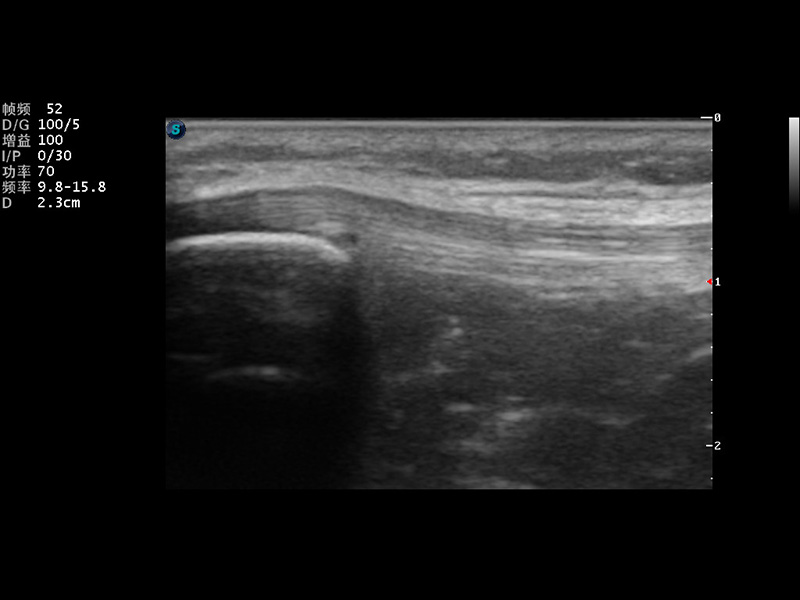

S9便携式彩色多普勒超声诊断仪是九州酷游研发的高端便携彩超设备,外观设计新颖、产品性能卓越。S9在便携超声领域采用了突破传统的触摸屏交互设计,并以先进的软件硬件技术和设计理念,为您带来清晰的图像质量、稳定的工作性能和便捷的操作体验。